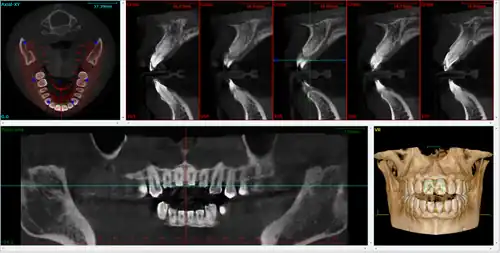

It is possible for both tooth decay and periodontal disease to be missed during a clinical exam, and radiographic evaluation of the dental and periodontal tissues is a critical segment of the comprehensive oral examination. The photographic montage at right depicts a situation in which extensive decay had been overlooked by a number of dentists prior to radiographic evaluation.

There is increasing use of CT (computed tomography) scans in dentistry, particularly to plan dental implants;[19] there may be significant levels of radiation and potential risk. Specially designed CBCT (cone beam CT) scanners can be used instead, which produce adequate imaging with a stated tenfold reduction in radiation.[20] Although computed tomography offers high quality images and accuracy,[21] the radiation dose of the scans is higher than the other conventional radiography views, and its use should be justified.[22][23] Controversy surrounds the degree of radiation reduction though as the highest quality cone beam scans use radiation doses not dissimilar to modern conventional CT scans.[24]

Cone beam computed tomography

Cone beam computed tomography (CBCT), also known as digital volume tomography (DVT), is a special type of X-ray technology that generates 3D images. In the recent years, CBCT has been developed specifically for its use in the dental and maxillofacial areas[4] to overcome the limitations of 2D imaging such as buccolingual superimposition.[25] It is becoming the imaging modality of choice in certain clinical scenarios although clinical research justifies its limited use.[4]